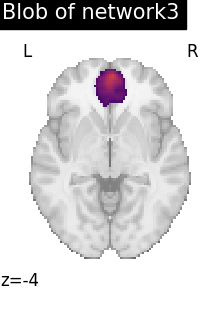

# To reduce the complexity, we choose to display all the regions

# extracted from network 3

regions_indices_network3 = np.where(np.array(extraction.index_) == 3)

for index in regions_indices_network3[0]:

cur_img = index_img(extraction.regions_img_, index)

coords = find_xyz_cut_coords(cur_img)

plotting.plot_stat_map(

cur_img,

display_mode="z",

cut_coords=coords[2:3],

title="Blob of network3",

colorbar=False,

cmap="inferno",

vmax=15,

)